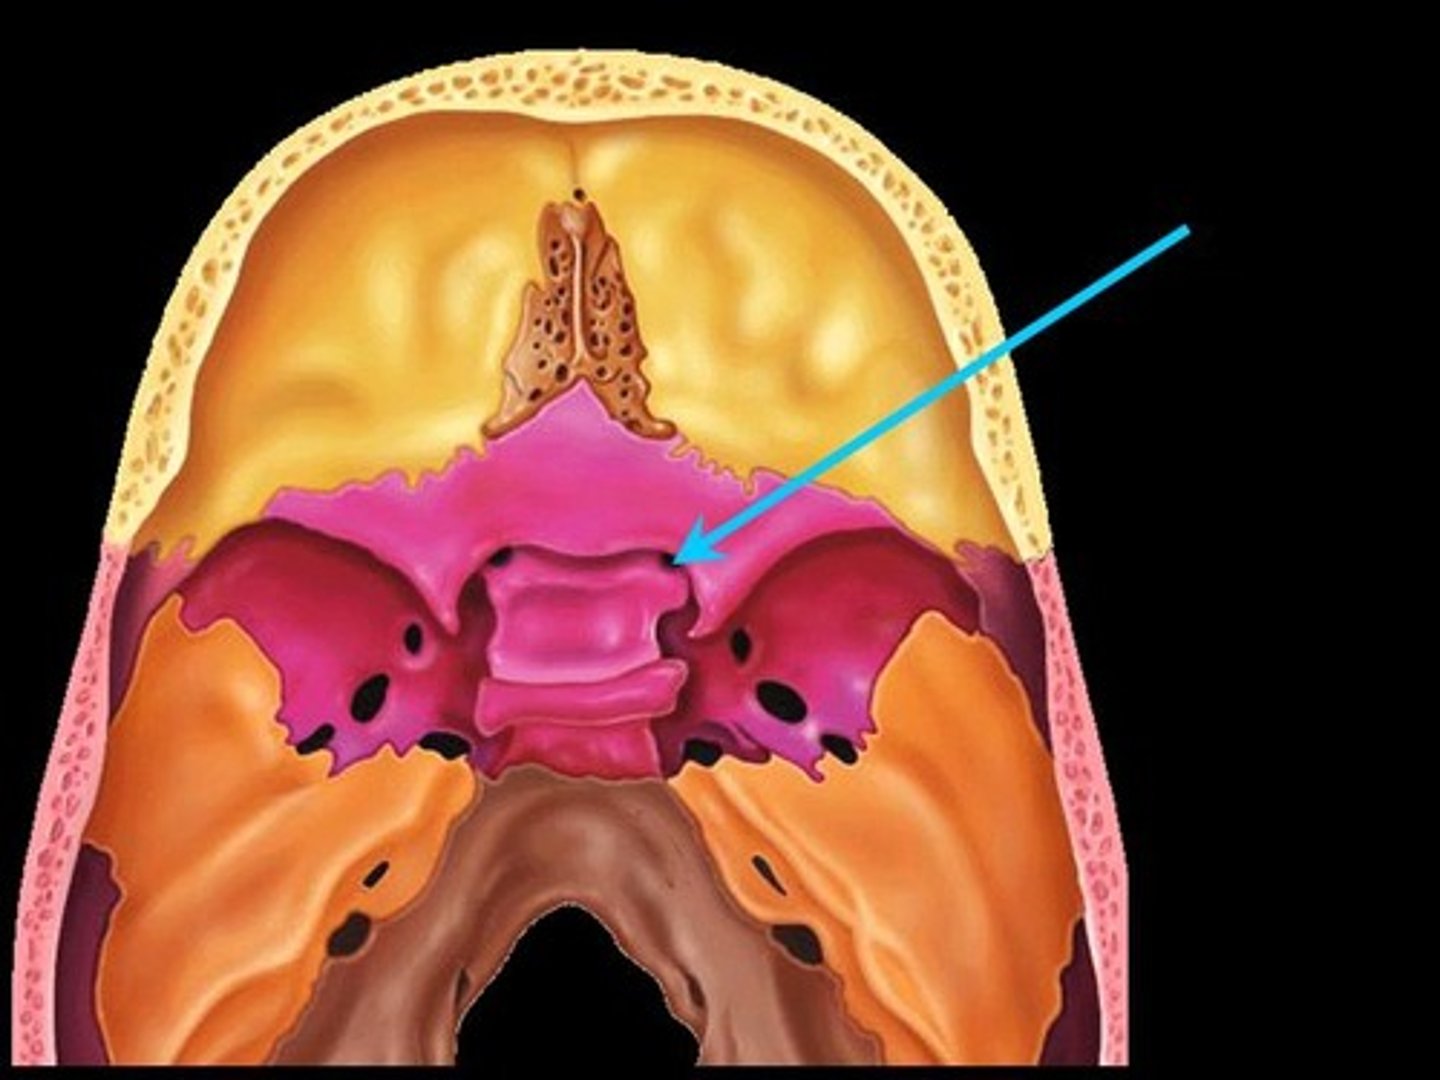

Sella turcia (hypophyseal fossa)

Greater wings

Less wings

Cribiform plate

Crista galli